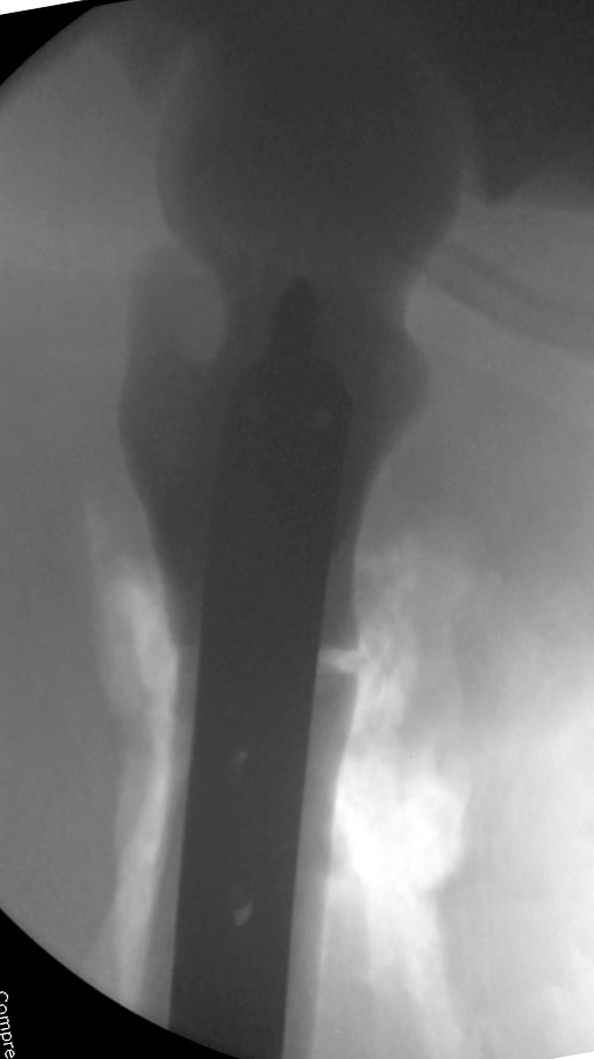

После неудачной попытки скелетного вытяжения в первом мед.учреждении, после осмотра снимков и изучения истории, поставили диагноз “Остеопетроз” или мраморная болезнь, редкая наследственная костная паталогия, где имеется нарушение формации остеокластов.

Конечно, было бы идеальным применение интрамедуллярного остеосинтеза, но учитывая прежний собственный опыт (лечил перелом бедра) и

публикации, предупреждающие о трудностях при обработке кости (иногда из-за неподготовленности инструментария результатом была неадекватная фиксация перелома, или перенос операции из-за фактора усталости оперирующего персонала), решили применить пластину (и в этом же случае был выбран Synthes plate, так что представитель за два дня

Заказаны были дополнительные различные дрели, и на следующий день, усиленной бригадой, больного прооперировали, потратив на каждое отверстие около 25-35 минут, хотя сверлили с охлаждением по нарастающей по диаметру сверл и с их заменой каждые 2 мм сверления.

Теперь стоит задача со сращением перелома, из-за отсутствия литературных данных по применению костных стимуляторов при остеопетрозе, и не зная как поведет в этой среде Grafton, все таки надеюсь, что даст толчок к стимуляцию, решил применить пастообразную деминерализованную костную матрицу, расположив спереди между отломками.